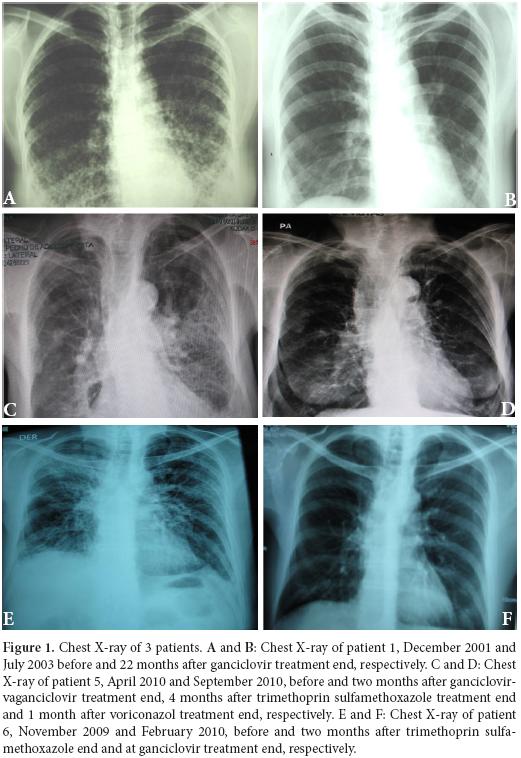

Patient 1: A 38 year-old woman, heterosexual with no history of promiscuity, was admitted to a medical care hospital on January 21th, 2002 with a 3 month history of chills, fever and coughing with sputum production, progressive dyspnea, fatigue, weakness, anorexia and 10 kg weight loss. At the time of presentation she was being treated with 4 antituberculosis drugs for 34 days determined by bilateral reticulonodular interstitial infiltrates in her chest X-ray (Figure 1A) and chest computed tomography (chest CT). Samples of bronchoalveolar lavage (BAL) were mycobacteria stain and culture negative. Transtracheal wash was fungus stain and culture negative too. She had a low level of hemoglobin (11.3 g/dl), hematocrit (37.7%), peripheral blood lymphocytes (699 /mm 3), CD4+ T cells/mm3 92 (13.2%) and CD8+ T cells/mm3 144 (table 1 and Figure 2:A-C). Lung biopsy showed nonspecific focal, interstitial fibrosis, a few Pneumocystis jiroveci (P. jiroveci) and DNA of EBV by polymerase chain reaction (PCR). The patient's vital signs showed a temperature that ranged from 38 °C to 39.5 °C, respiratory rate of 40, pulse of 140, weight of 43 kg, height 1.62 m. Treatment with trimethoprin sulfamethoxazole and prednisone for 21 days was commenced on February 6th. The patient's temperature fell to 38 °C and pulse to 128, but she persisted tachypneic with a respiratory rate of 56 and coughing. Her weight decreased to 38 kg.

The result of serum antibodies of different viruses included CMV, EBV and HIV test are shown in table 1. On April 16th, 2002, treatment with intravenous ganciclovir and 80.000 U of interferon α sublingual every 8 h was commenced. Five days later her vital signs had improved with a respiratory rate of 36, pulse of 88 and weigh of 42 kg. One month after ganciclovir was commenced the lymphocytes count had risen to 3.148/mm3 and CD4+ T cells count was 322 cells/mm3 (10.2%) and CD8+ T cells count was 228 cells/mm3 (Figure 2:A-C). She was treated with ganciclovir for 5 months and INFα for 8 months. In June 2003, her weight was 60 kg, respiratory rate 20, pulse 80 and her chest X-ray had only minimum residual lesions in the lower lung lobes (Figure 1B). On October 14th, 2010 the patient was asymptomatic and her lymphocytes count was 1. 988/mm3, CD4+ T cells were 503/mm3 (25.3%), with 684 CD8+ T cells/mm3. Also her CD4+/CD8+ T cells ratio was normal (Figure 2: A-D).

Patient 5: A 74 year-old woman with history of osteoporosis, gastric cancer 30 years before, cigarette smoke exposure, chronic obstructive pulmonary disease with spontaneous pneumothorax 8 months before, was attended by Staphylococcus aureus methicillin sensitive bacteremia and pneumonia. She was treated since April 1st, 2010 with piperacillin-tazobactam and mechanical ventilation support. The hemograms of April 1st and 9th showed lymphocytopenia of 610 mm3 and 450 mm3 respectively. A chest CT showed findings of pulmonary thromboembolism, alveolar infiltrates in the left lung and interstitial fibrotic lesions, bulla, bilateral pleural effusion and right cardiomegaly (Figure 1 C). On April 11th, she had 109 CD4+ T cells/mm3 (17.9%) and 43 CD8+ T cells/mm3 (Figure 2: A-C). On April 9th she was treated with trimethoprin sulfamethoxazole for Stenotrophomonas maltophlia nosocomial pneumonia and empirical for P. jiroveci pneumonia. Predisone plus ganciclovir were added. The results of antibodies to different virus are in table 1. On April 27th, her lymphocytes count increased to 730/mm3. On April 30th, she could be removed from mechanical ventilatory support. She was treated with valganciclovir for 3 months and voriconazole for 4 months, by repeated isolation of Aspergillus fumigatus in bronchial secretions without a lung biopsy because of the high risk of the procedure. In August she had an improvement in her immunology alterations which are shown in table 1 and Figure 2: A-D. She also improved pulmonary infiltrates (Figure 1: D).

Patient 6: A 62 year-old professor was diagnosed on November 7th, 2010 with coughing, adynamia, fatigue and progressive dyspnea for four months before. He had antecedents of amigdalectomy at 19 years old, hepatitis at 16 years old, appendectomy at 59 years old, red blood cells transfusion during diverticulitis with peritonitis in January 2006 and chronic renal diseases treated with hemodialysis until May 2007. Also he had a history of oral ulcers on two occasions in 2008 and urinary infection in January 2009. At the moment of medical examination, his chest X-ray showed diffuse bilateral interstitial infiltrates (Figure 1E). The chest CT had reticular infiltrates greater in the right upper lung lobule, bronchiectasis, irregular interstitial subpleural thickening and ground-glass opacities superimposed. Previously, he had tuberculin test on 11 mm but the ZN smear mycobacterial and fungus culture of BAL and three ZN sputum were negative.

On November 17th, 2009, the lymphocytes count was 681/mm3, CD4+ T cells were 279 / mm3 (40.9%) and CD8+ T cells were 110/mm3 (table 1 and Figure 2: A-C). He had IgG and IgM anti CMV negative but CMV PP65 antigen positive table 1. On November 22th, 2009 a induced sputum calcofluor stain showed structures compatible with P. jiroveci. On November 23rd, he was treated with prednisone and trimethoprin-sulfamethoxazole for 3 days followed by clindamycin and primaquine for 18 days. On November 26th, he started ganciclovir for 3 months. On December 17th the fever, cough, dyspnea, fatigue and weight loss had improved. On December 17th, 2009 the lymphocytes count was 957/mm3, CD4+ T cells were 318/mm3 (33.2%) and CD8+ T cells were 182/mm3. The improvement of different immunology alterations, after gancicolvir treatment, can be seen in table 1 and Figure 2:A-D. The radiology pulmonary infiltrates improvement can be seen in the Figure 1: F.